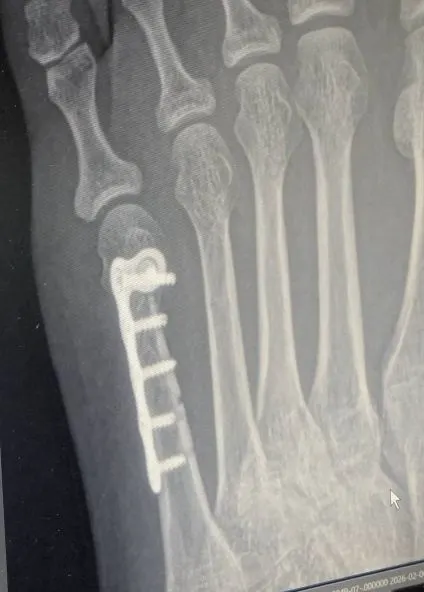

原本我還在猶豫,還在掙扎著是否有最後一絲不開刀的希望,但老公不等我遲疑,馬上請醫生幫我排刀,就這樣在下午便進了開刀房,打了鋼釘,補了骨泥,老公還傳了照片給孩子,說我成了鋼鐵人XD(這樣以後出國過海關,會不會嗶嗶叫啊?)